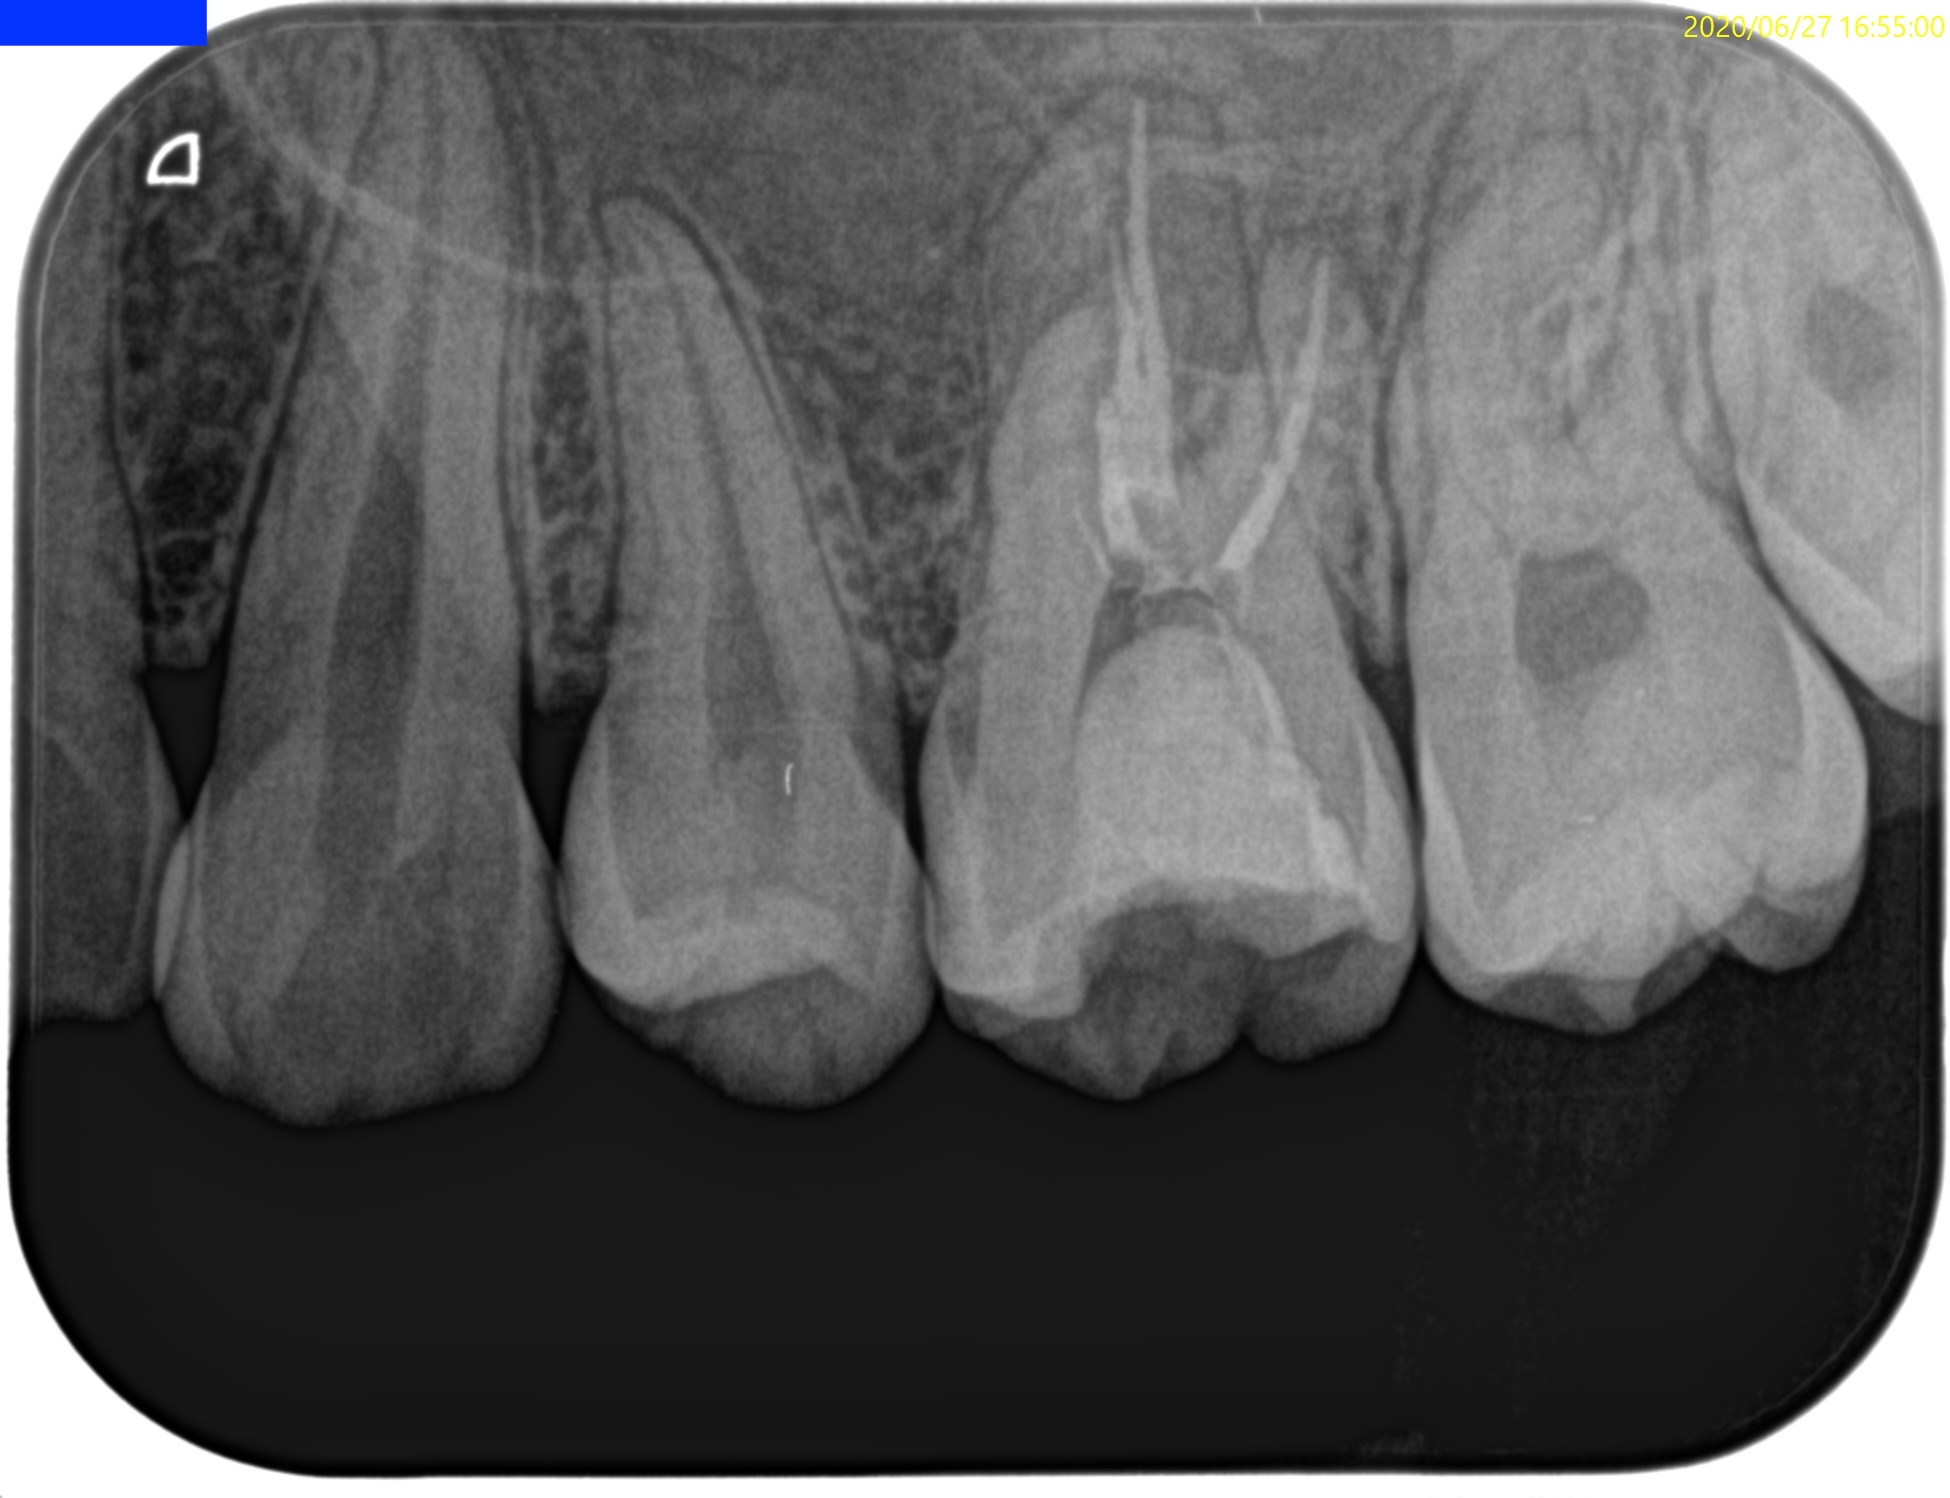

Pre-op Endo test(2020.6.27)

この時代は当歯科医院にCBCTがない時代で、非外科的な治療であるので撮影を外部へ依頼していない。

Pulp Dx: Previously treated

Periapical Dx: Symptomatic apical periodontitis

Recommended Tx: Re-RCT